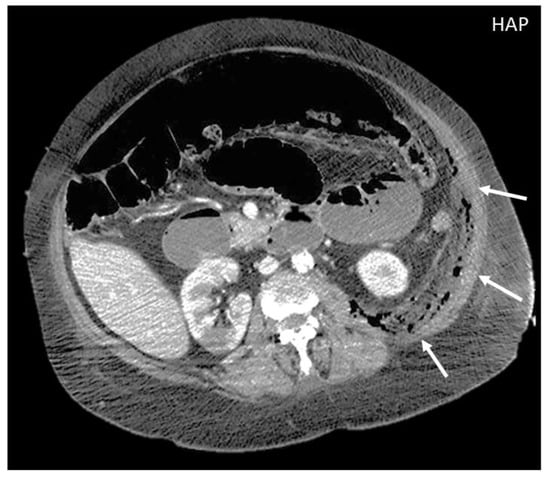

Figure 2. CT appearance of necrotizing fasciitis in a 58-year-old woman with a recent left lower limb open wound who arrived at the ER in septic shock. Arterial phase axial CT scan reveals the presence of free air in the fascial planes of the left lateral and posterior abdominal wall, with fascial thickening and lack of muscular enhancement, as compared to its counterpart (arrows). These elements are suggestive of necrotizing fasciitis. The patient was promptly referred to surgery, but she died on the operatory table.